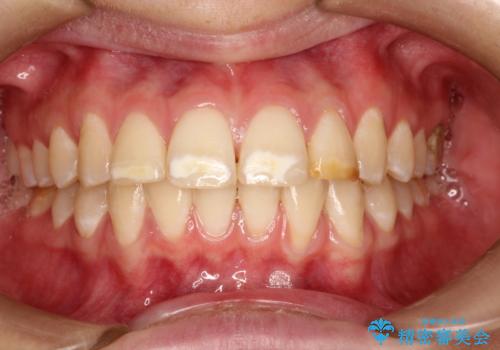

- 前歯をきれいにしたいとのご希望がありました。

生まれつき歯の色が白濁しているところや、黄色くなっているところがあり、セラミッククラウンに審美的改善を行うこととしました。